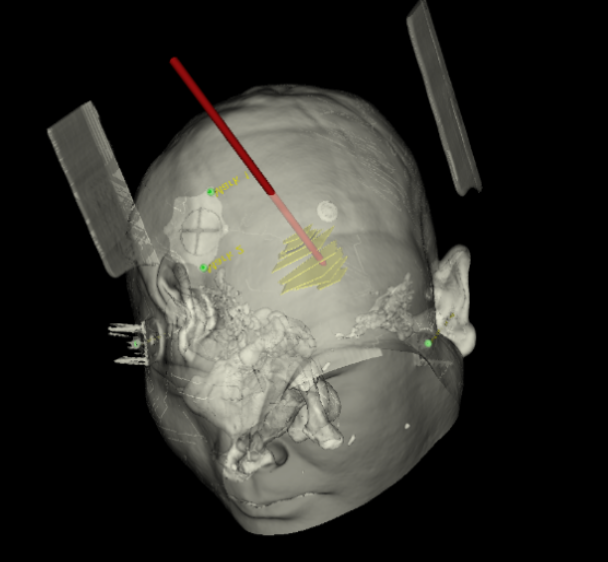

手術(shù)日當(dāng)天,醫(yī)生團隊通過手術(shù)計劃系統(tǒng)為患者制定手術(shù)靶點及最安全的入顱路徑,隨后將手術(shù)規(guī)劃導(dǎo)入手術(shù)室的機器人當(dāng)中。

實際手術(shù)時,機器人在幾分鐘內(nèi)就完成了空間注冊,機械臂在定位儀的引導(dǎo)下自動定位,準確鎖定靶點。

韓帥醫(yī)生借助機器人操作平臺順利抽出血性液體15ml,與術(shù)前軟件計算的血腫量完全一致,手術(shù)在30分鐘內(nèi)順利完成。